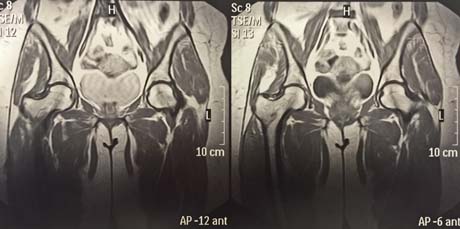

MRI: left femoral head osteonecrosis (white arrow)

Magnetic resonance imaging of the hip after 5 months post-op and the injection of stem cells. Osteonecrosis of the femoral head has subsided completely. The patient is fully cured.

After surgery on the patients right hip the symptoms began to subside immediately. The patient gradually weight bearing the right limb, and five months after it is fully functional without any pain and stiffness in the hip joint.